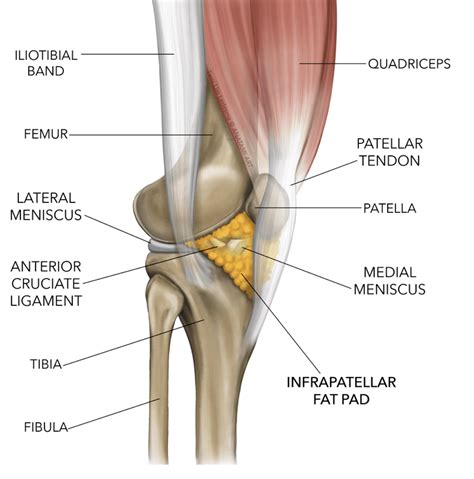

To understand why this condition is so painful, it helps to know the role of the infrapatellar fat pad. Think of it as a specialized, cushioned shock absorber. It sits between the patellar tendon and the femur, providing lubrication and stabilization to the front of the knee joint. Under normal circumstances, this fat pad is flexible and moves out of the way as you bend or straighten your leg. When Fat Pad Impingement occurs, the tissue gets caught between the bones of the knee joint, leading to localized inflammation, swelling, and a cycle of chronic pain.